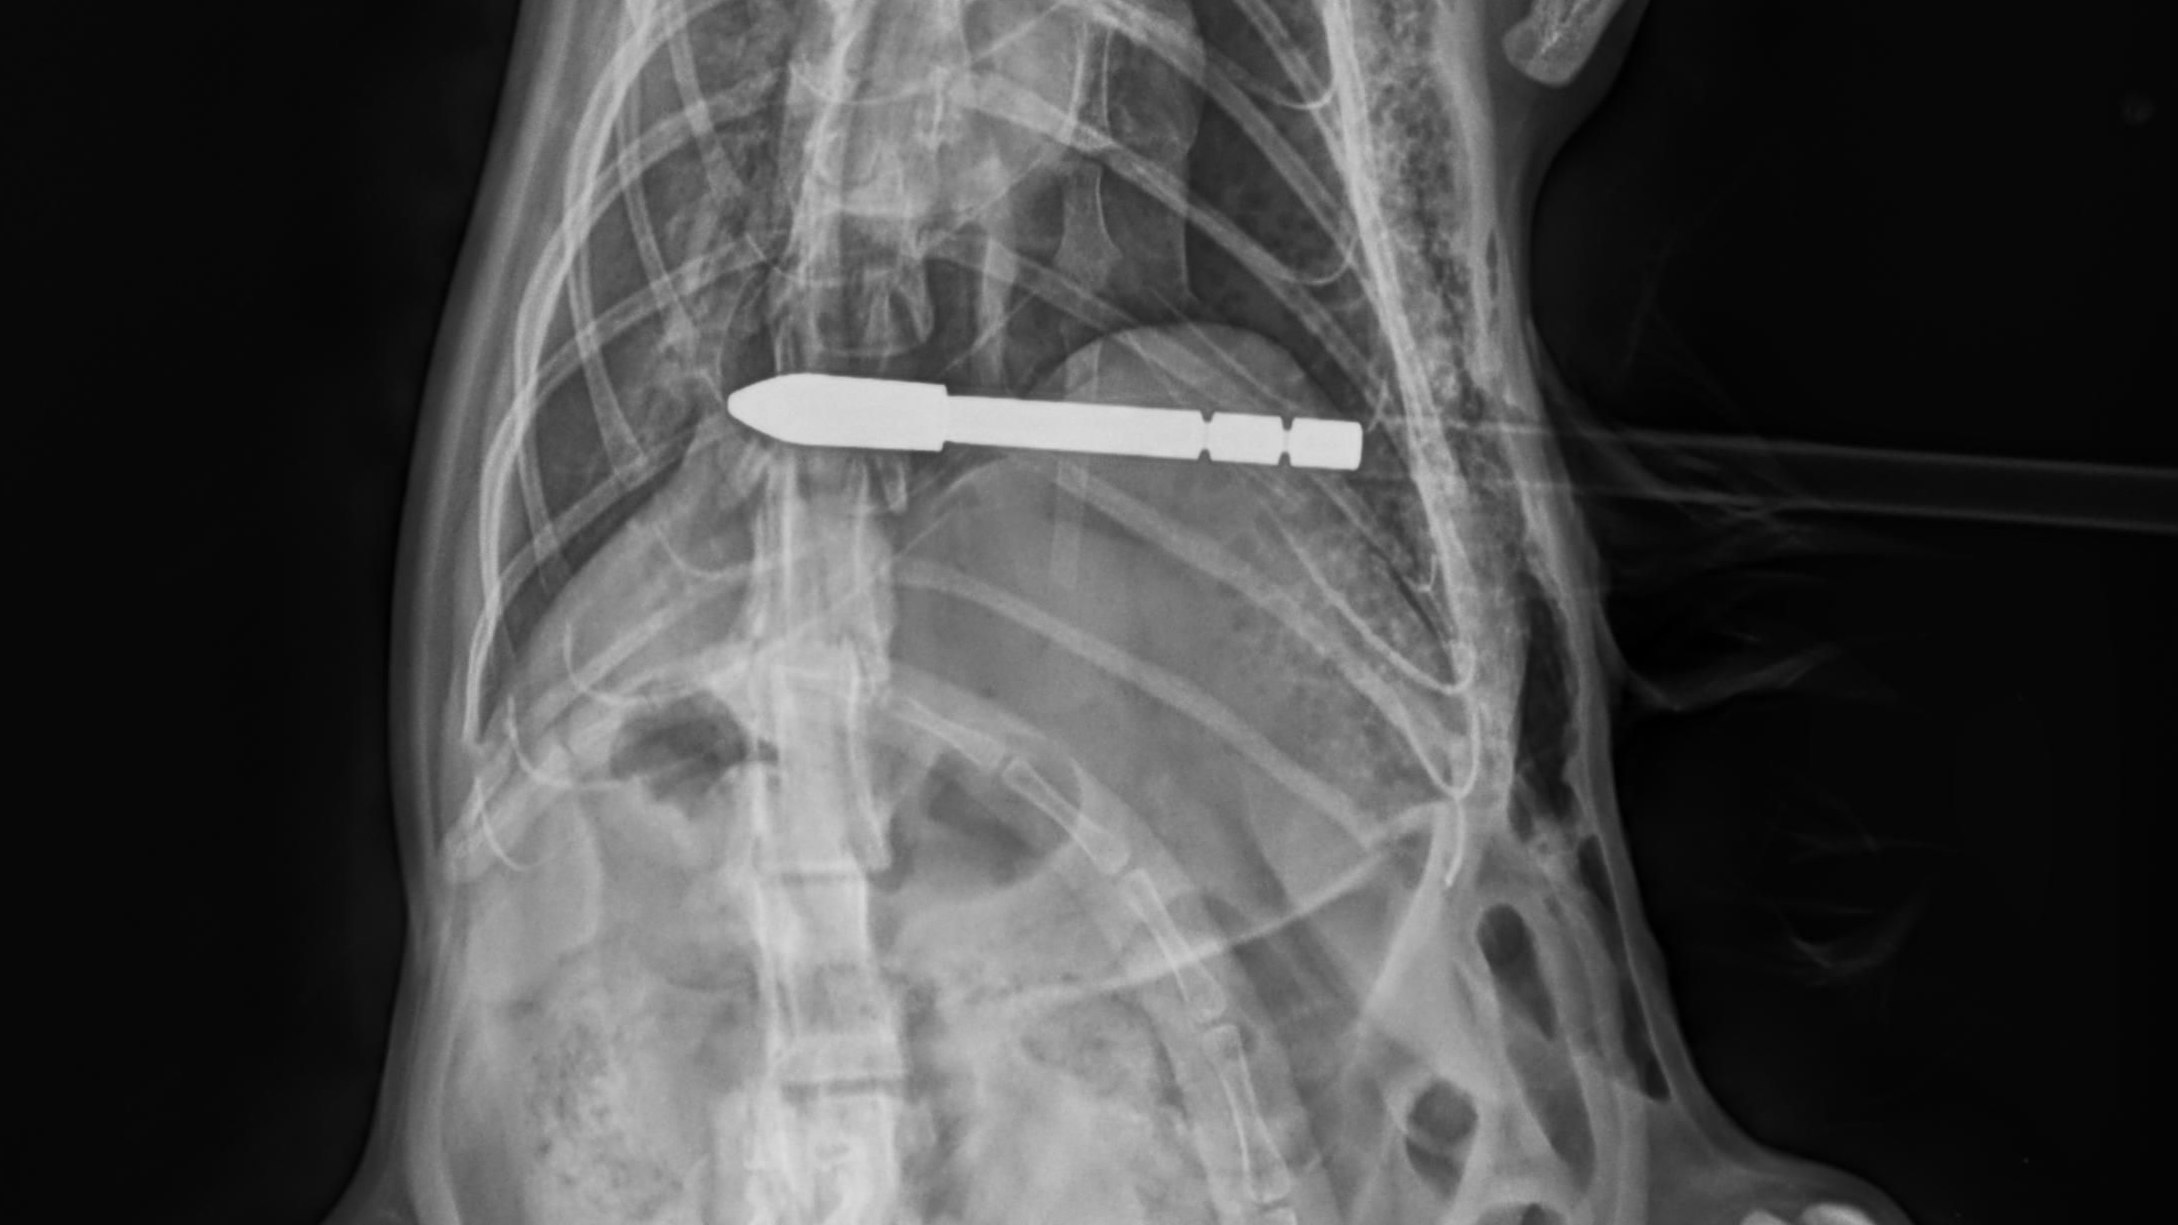

Der Pfeil durchbohrte die Katze.

Am 13. Juli 2022 in den Nachmittagsstunden schoss ein bisher unbekannter Täter im Bereich Zmuln, Gemeinde Liebenfels, Bezirk St. Veit an der Glan, mit einem Pfeil auf eine freilaufende Katze. Der Pfeil durchbohrte die Katze, verletzte diese im Bereich der Lunge und blieb in ihr stecken. Die Katze wurde in eine Tierklinik in Klagenfurt gebracht und der ca. 80 cm lange Pfeil operativ entfernt. Das Tier befindet sich derzeit in äußerst kritischem Zustand. Die Polizeiinspektion St. Veit an der Glan ersucht um sachdienliche Hinweise in diesem Fall.